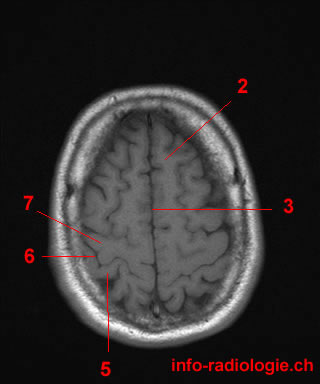

1. What is it?

The question is referring to the anatomical structure known as the right maxillary sinus, which is one of the paranasal sinuses located in the skull. The correct answer is the right maxillary sinus as indicated by option 1. Options 2, 3, and 4 are incorrect as they do not represent the structure being asked about.